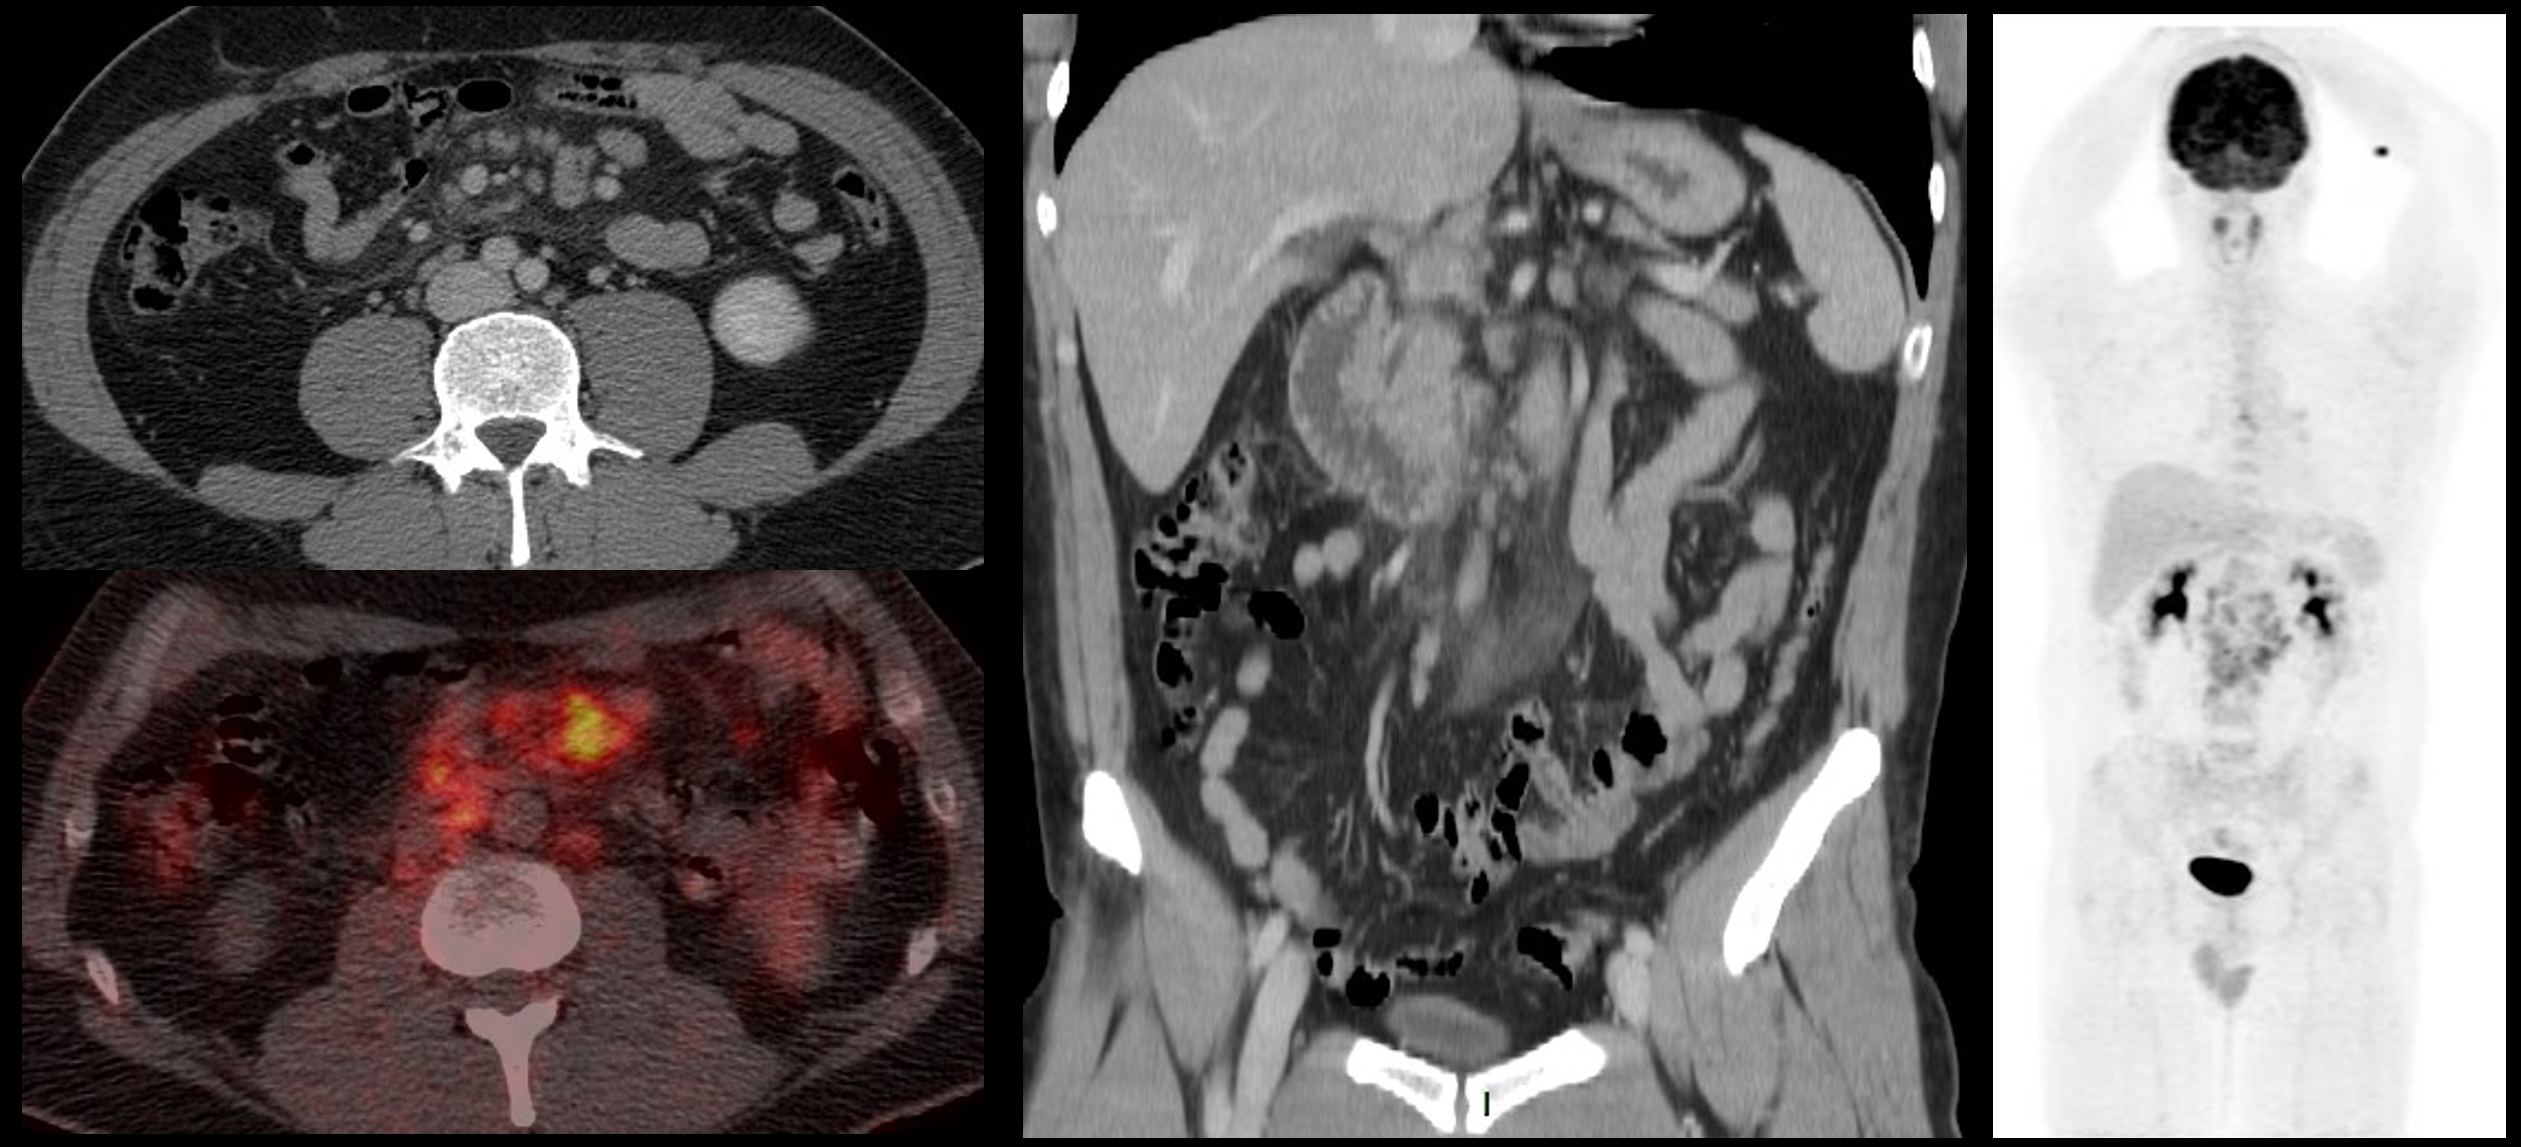

Después del análisis consensuado de los tres observadores en busca de paniculitis mesentérica, solo un caso no llegó a acuerdo. Se trató de un cáncer de próstata evaluado positivo por dos observadores y dudoso por un tercero, que se consideró finalmente con paniculitis mesentérica. La prevalencia de paniculitis mesentérica en el grupo oncológico fue de 5,2% (100/1911). La neoplasia con mayor frecuencia de esta patología fue el linfoma no Hodgkin con 16,1% (34/211), 56% de ellos de subtipo folicular. Uno de estos casos se muestra en la Figura 1.

Hombre de 42 años con LNH folicular grado I-II con Ki67: 20%.

A izquierda cortes axiales de la TC y fusión de las PET/CT muestran signos de paniculitis mesentérica con linfonodos hipercaptantes (SUVmax 7,3), de mayor actividad que el hígado (SUVmax 2,7). Imagen central muestra TC con aumento de densidad y volumen de la grasa mesentérica. Imagen derecha: MIP del PET que muestra solo compromiso mesentérico.

Fuente: preparado por los autores a partir de un caso incluido en la casuística.